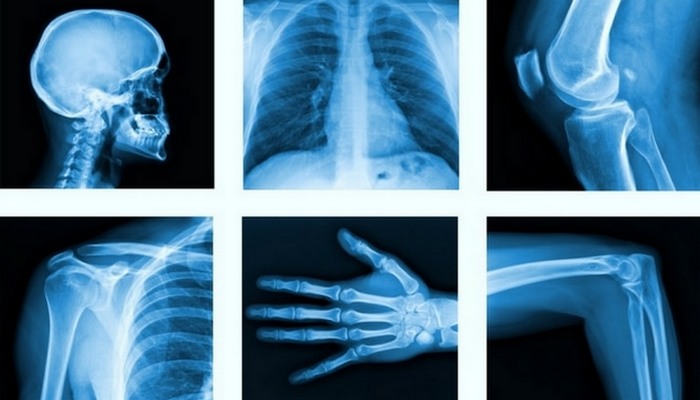

2. Рентген

Прорыв в медицине: рентген.

Трудно представить правильную диагностику и лечение травм, таких как переломы, без технологии рентгеновского изображения. Рентгеновское излучение было случайно обнаружено, когда немецкий физик Вильгельм Конрад Рентген изучал процесс прохождения электрического тока через газ с чрезвычайно низким давлением.

Ученый заметил, что в затемненной комнате электронно-лучевая трубка, покрытая барием-платиноцианидом, светится флуоресцентным светом. Поскольку катодные лучи невидимы, он не знал, что это за лучи вызывают такое свечение и назвал их рентгеновскими. Ученый получил первую в истории Нобелевскую премию по физике в 1901 году за свое открытие.